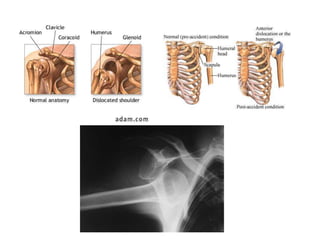

• DISLOCATION

Dislocation